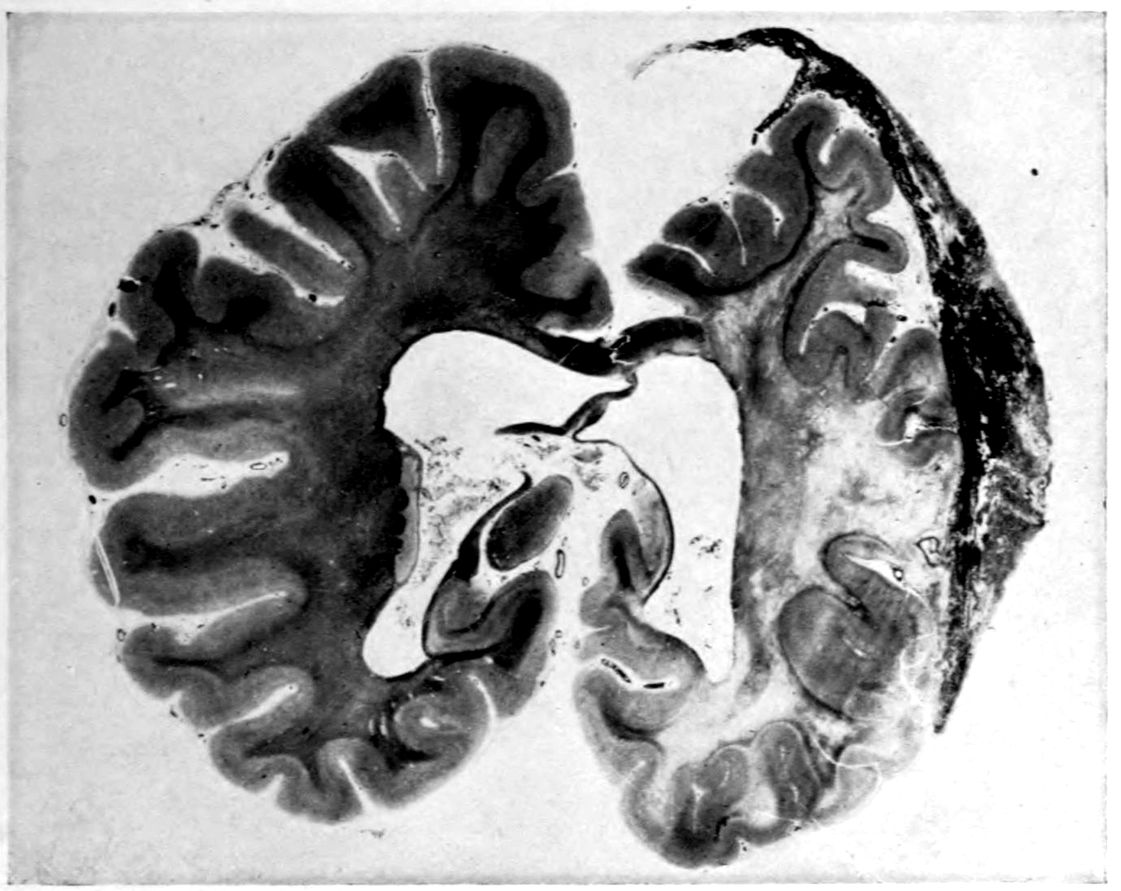

Case 4. James Pierce was an almshouse transfer to the Danvers Hospital in his fiftieth year. He died three years later. The accompanying brain pictures demonstrate so extensive a lesion of the left hemisphere that it is of great interest to determine if possible the genesis and course of his disease. It appears that syphilis had been acquired somewhere about the age of 38 or 40, so that the total duration of the process was between 13 and 15 years. In Pierce’s forty-third or forty-fourth year, he had a shock while walking in the streets of his native city, whereupon he was subsequently transferred to the Danvers Hospital, whose data have been summed up as follows (we are obliged to Dr. Charles T. Ryder for these data):

Head: Calvarium of moderate thickness; diploë present; dura slightly adherent over bregmatic region. Longitudinal sinus contains cruor clot. Dura is somewhat thickened and slightly more opaque than normal. Pacchionian granulations, small but fairly numerous. Pia contains throughout a considerable excess of clear 44serous fluid. The convolutions in general are of good breadth and proportion. There is an atrophic area roughly circular in outline and about 2 cm. in diameter in the posterior part of the right third frontal convolution corresponding to Broca’s area on the opposite hemisphere. The space thus formed is filled with edema held by the pia. On the left side is a similar subpial collection which covers the site of the posterior portions of all of the third frontal convolutions, parts of the lower end of the precentral convolution, and the whole of the first temporal convolution, which have disappeared entirely. The basal vessels show slight changes.

Cerebellum and basal ganglia are grossly normal.

The spinal membranes are negative. The regions of the pyramidal tracts in the cord are firm, project slightly from surface of section, and are china white.

Summary: Here is a picture made up almost purely of Vascular Neurosyphilis, with Secondary Spinal (Pyramidal Tract) Changes. Doubtless the genesis of this picture is allied to that of Case 1 (Alice Morton) and to that of the terminal vascular complications in a tabetic, Case 2 (Francis Garfield).

The absence of meningeal and parenchymatous (i.e., outside the region of necrosis produced by the vascular disease) lesions is characteristic of an important group of neurosyphilitic diseases. It is clear that the case, although one of extensive lesions, is not one of diffuse lesions in the sense of Case 1 (Alice Morton).

Vascular neurosyphilis—effects of syphilitic thrombosis of Sylvian artery 10 years before death. (Case 4.)

Case 4. (See previous figure for brain lesion.) Three levels of the spinal cord showing unilateral pyramidal tract sclerosis, 10 years after cerebral thrombosis.